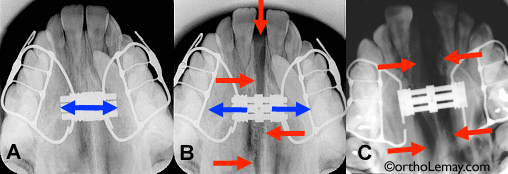

(A) Avant l’activation de l’appareil; la vis d’expansion et la suture sont fermées.

(B) Vers la fin de l’expansion, la vis est ouverte (flèches bleues) et la suture est ouverte de plusieurs millimètres. Les flèches rouges indiquent la zone foncée qui représente l’ouverture de la suture.

(C) Autre cas montrant une très grande ouverture lors de l’expansion maxillaire. La vis d’expansion a été ouverte de 14 mm et la zone sombre de la suture est bien visible.